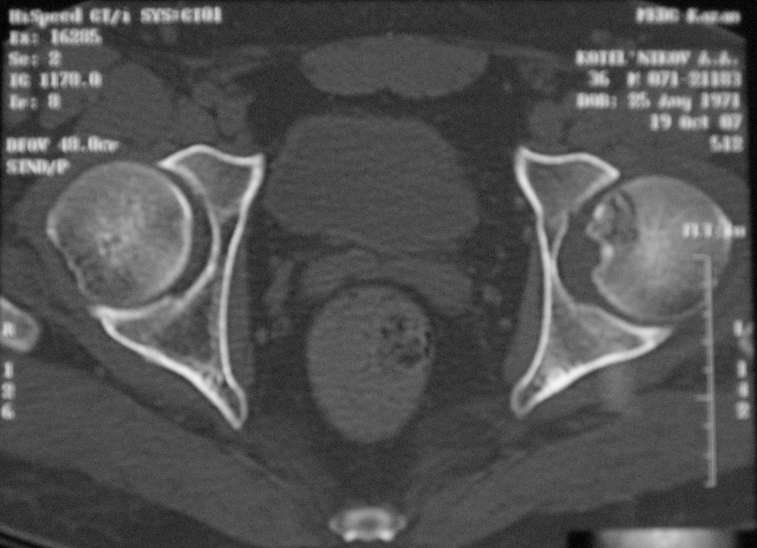

Молодой человек, 37л. Начало заболевания сентябрь 2007, резкие боли в области лев. тазобедренного сустава, повышение температуры до 39 гр., в течение недели, лабораторные данные: лейкоцитоз со сдвигом влево. Посев крови на стерильность возбудителя не выявил. По данным Рг, РКТ выставлен диагноз: Левосторонний коксит? Асептический некроз? Проводилось лечение: цефсон в/в неделю, иммобилизация кокситной повязкой 1 мес. Обратился повторно 10 дней назад с жалобами на сильные боли в левом тазобедренном суставе, белая кровь – нормограмма, СОЭ 46 мм/ч. На сегодняшний день: болей не отмечает. Лаб.данные: белая кровь – нормограмма, СОЭ 30 мм/ч. Рентген и РКТ прилагаем.

Рассмотреная тактика лечения: операционная биопсия.

При отрицательных данных за коксит - диагноз асептический некроз - эндопротезирование

При положительных данных за коксит какие методы могут быть использованы?